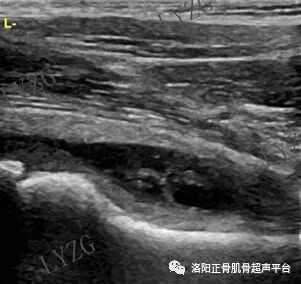

左侧髋关节前隐窝内积液并滑膜增生(呈不规则条带状)

右侧髋关节前隐窝内积液并滑膜增生(呈不规则团块状)

双侧对比,右髋关节前隐窝内未见大于2mm积液,左髋关节前隐窝内积液并可见丝带状滑膜增生

左髋关节前隐窝内及股骨头前方关节腔内均可见积液并可见少量团块状滑膜增生

双侧对比,右髋关节前隐窝内团声状中等回声增生滑膜,未见明显积液;左髋关节前隐窝内未见明显积液及滑膜增生

左髋关节前隐窝内积液并滑膜增生(呈条带状)

双侧对比,右髋前隐窝内积液,未见明显滑膜增生;左髋关节前隐窝内未见大于2mm积液,未见明显滑膜增生